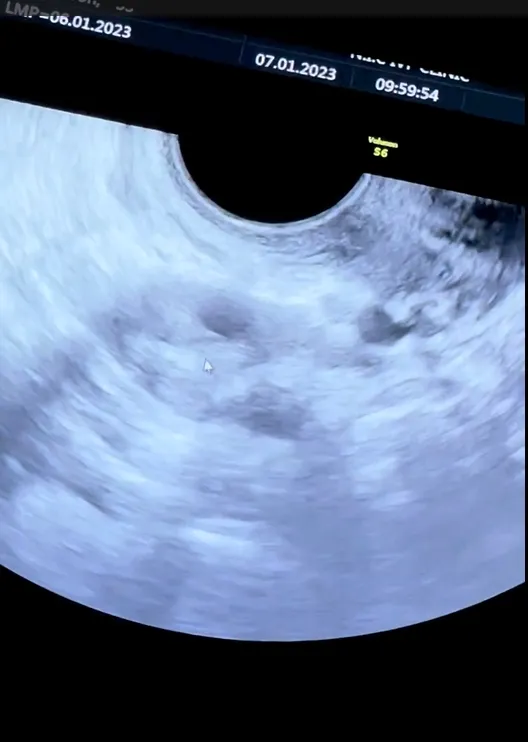

ล่าสุด สาวแอริน บอกขั้นตอนการผสมตัวอ่อนและการฉีดฮอร์โมน “การทำ ICSI (ผสมตัวอ่อน) รอบ 2 ของแอร์ค่ะ รอบนี้ยากกว่ารอบแรกไม่รู้ทำไมแม้ว่าไข่น้อยกว่ารอบที่แล้วอีก (รอบที่แล้ว 5 ฟอง รอบนี้ 4 ฟอง) อารมณ์สวิงขั้นสุดตั้งแต่เริ่มฉีดยากระตุ้นเอง จนถึงความอึดอัด อืด และหน่วงของท้อง อาจจะเป็นเพราะว่ารอบนี้ฉีดไปด้วยและทำงานเยอะด้วย หอบไปฉีดที่สิงคโปร์ด้วย เห็นอะไรก็ร้องไห้ เห็นหมาก็ร้องไห้ เหนื่อยแหละ งอแงสุดๆ แต่ก็ผ่านมาได้ค่ะ แม้ว่าหมอม้อนจะน่ารักขนาดไหนแต่ขอให้รอบนี้เป็นการเก็บครั้งสุดท้ายนะคะ เจอกันอีกทีตอนพร้อมเป็นหม่ามี๊เลยค่ะ (แต่เราเจอกันนอกรอบได้นะคะ)

“ขอขอบคุณคุณหมอม้อนสุดสวย @mont.sukprasert และพี่ ๆ พยาบาลทุกคนที่ @nicivfclinic มาก ๆ นะคะ รักกกก และ @benja_b ที่เป็นกำลังใจให้ตลอดและอดทนคอยปลอบเมื่อยามงอแง”